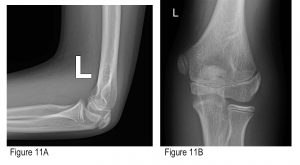

Figures 11A and B: AP and lateral of comparison (left) elbow. A shows a narrower medial condyle physis; B shows no anterior displacement of a distal humeral fragment.